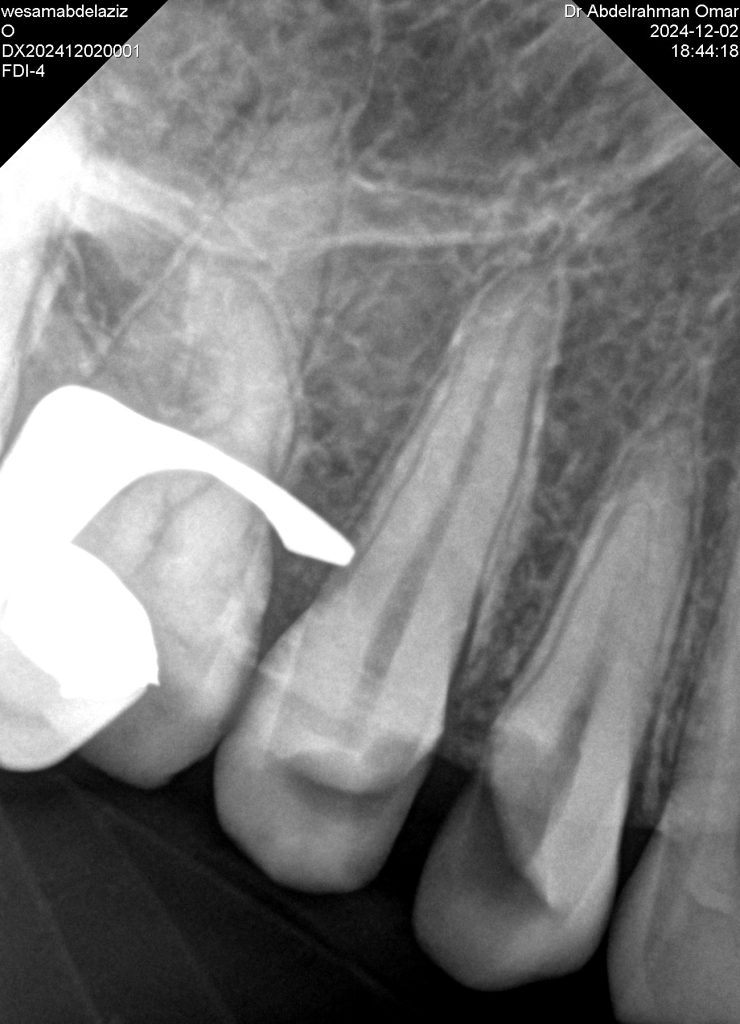

A 22 years old patient came to the clinic suffering from severe spontaneous pain. The diagnosis was acute irreversible pulpitis. The use of CDD is crucial here to ensure the CRE. After finishing endodontic treatment we used polyethylene fibers to enhance the bond strength and the strength of the tooth. Then the use of glass fibers (ever X composite) as a dentin replacement material before the final layer. After finishing. Polishing protocol with eve twist was done to gain the final polish